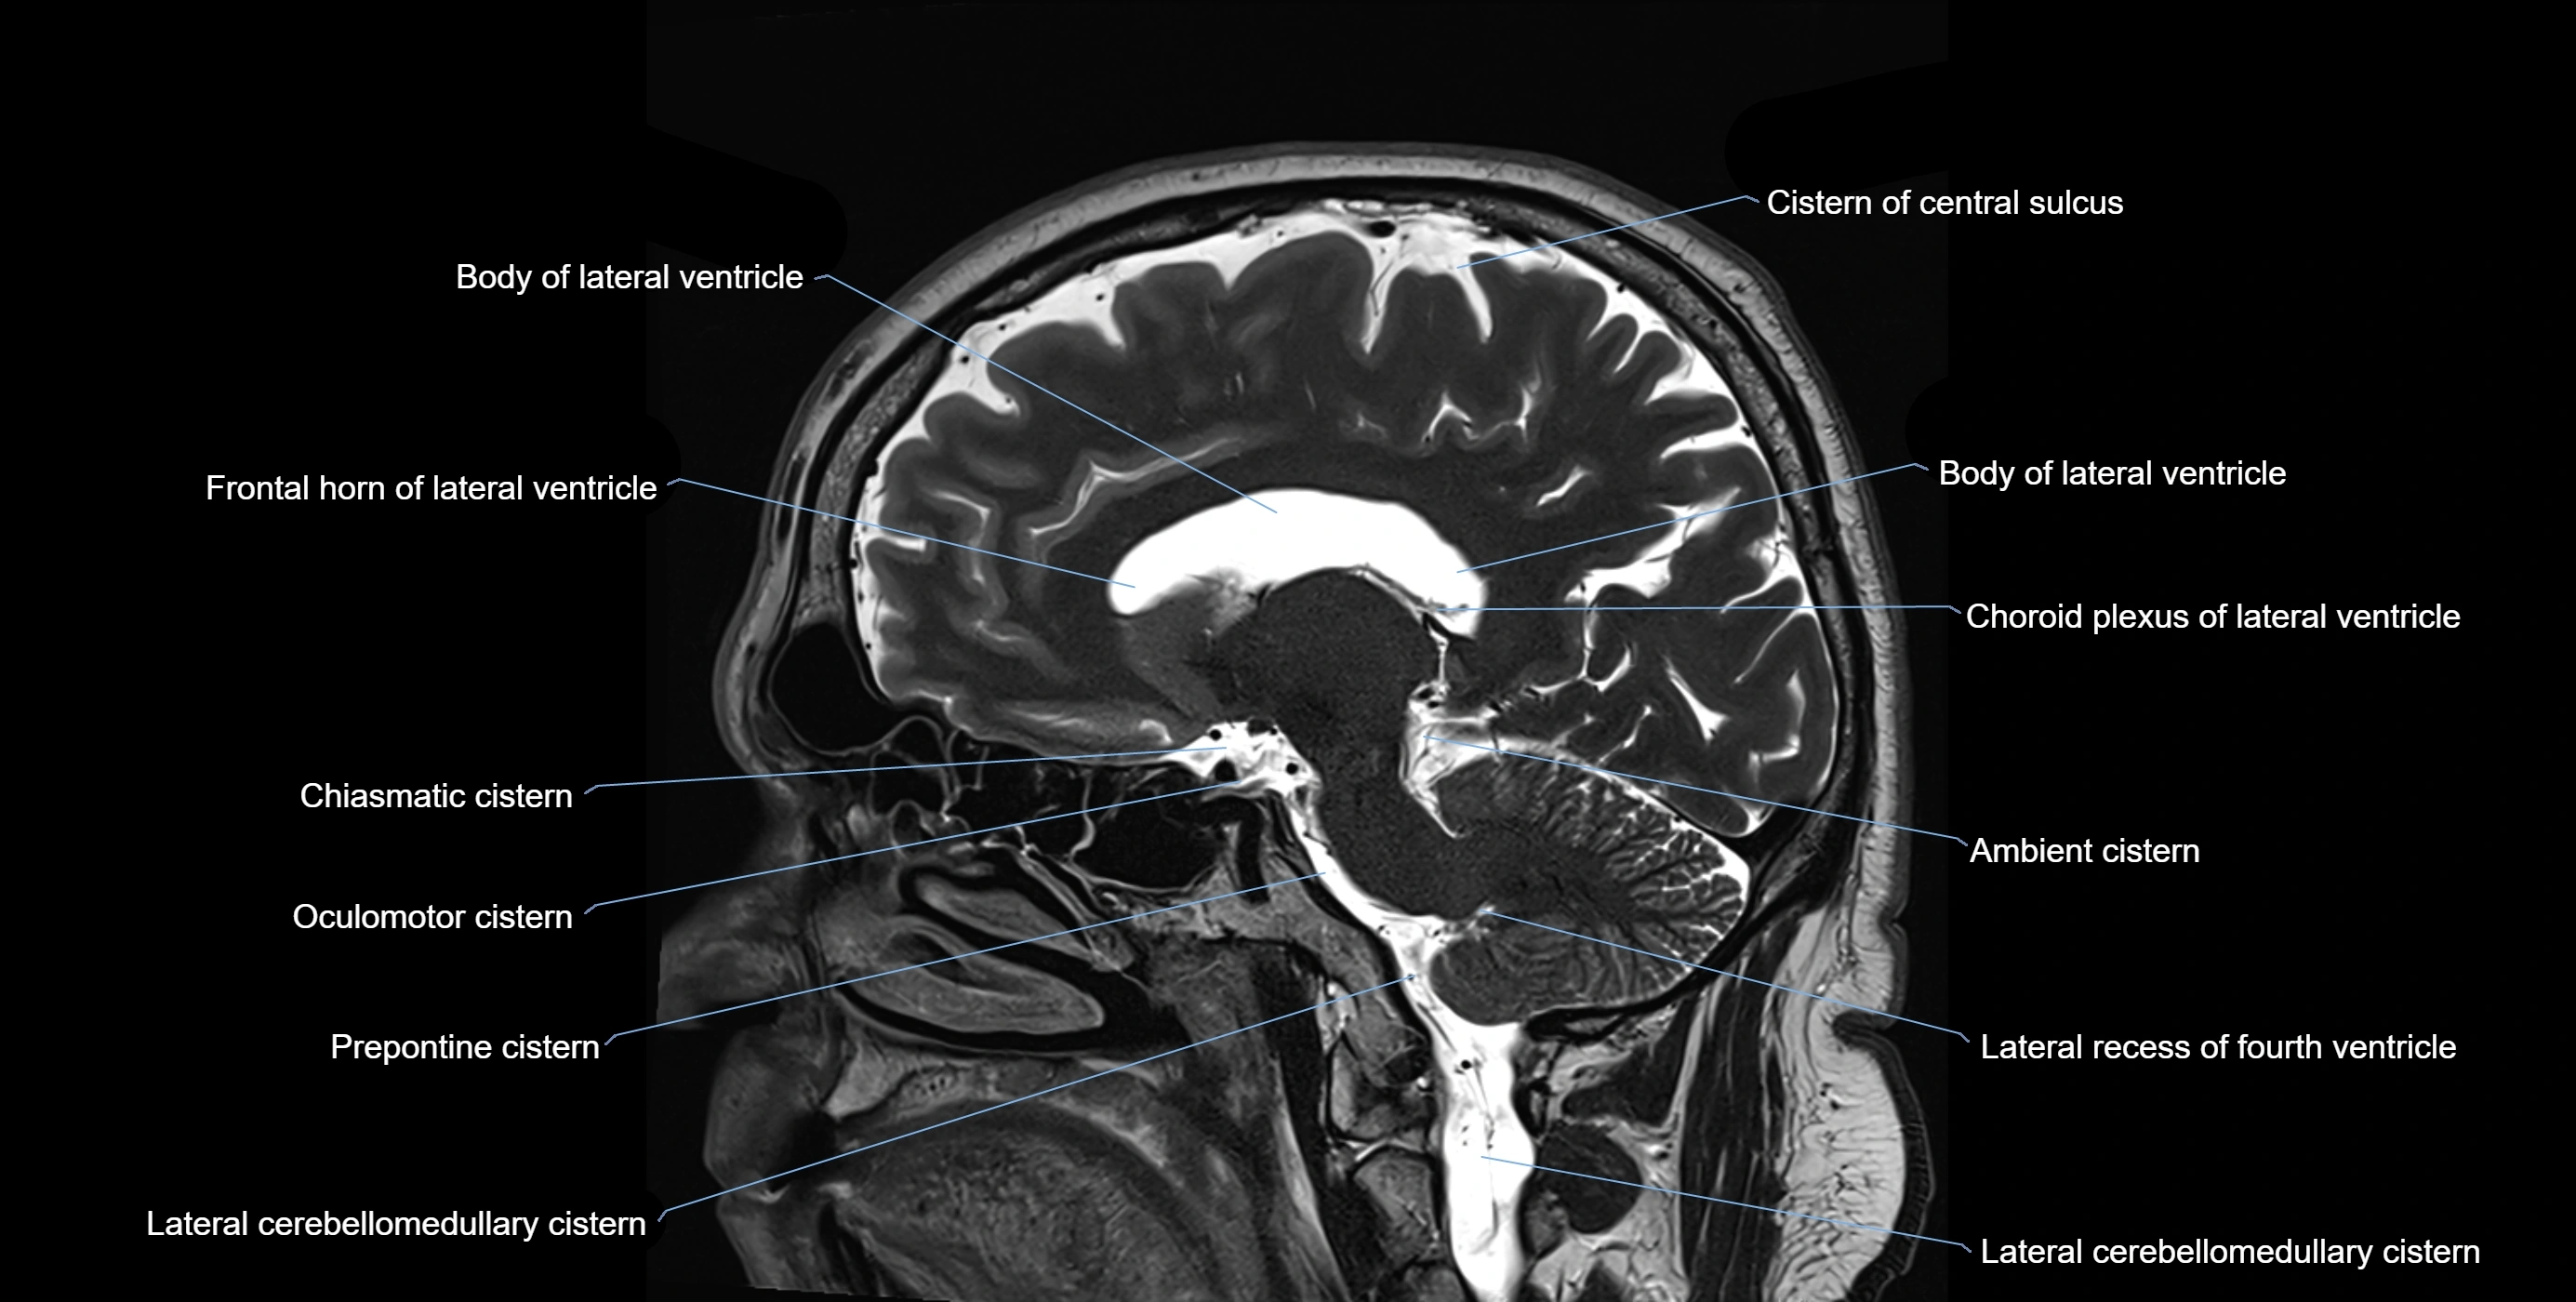

Ambient cistern

The ambient cistern is a paired, narrow, and elongated subarachnoid space located bilaterally along the lateral aspect of the midbrain. It serves as a conduit between the interpeduncular cistern anteriorly and the quadrigeminal cistern posteriorly. This cistern houses critical neurovascular structures, including parts of the posterior cerebral artery, superior cerebellar artery, trochlear nerve (cranial nerve IV), and the basal vein of Rosenthal. It plays an important role in the circulation of cerebrospinal fluid (CSF) and provides an anatomical corridor for various vessels and nerves passing around the midbrain.

MRI Appearance

• T1-weighted images:

• The ambient cistern appears as a region of low signal intensity, matching the dark appearance of CSF.

• Neurovascular structures within the cistern may appear as flow voids (signal loss from flowing blood) or as small dark linear structures.

• T2-weighted images:

• The cistern is hyperintense (bright) due to the high water content of CSF.

• Encapsulated vessels and nerves are seen as flow voids or hypointense lines within the bright background.